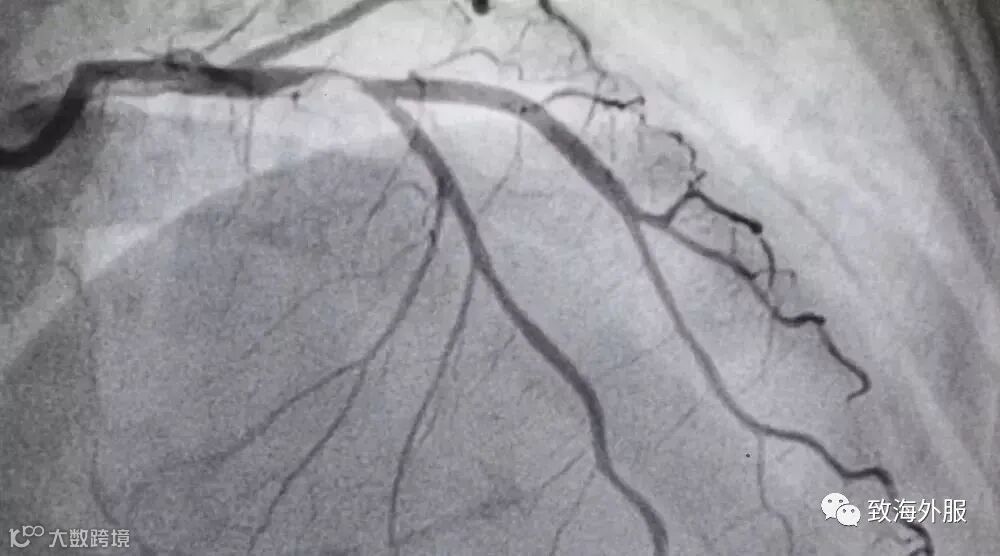

当颈动脉发生粥样硬化时,里面会出现硬化斑块,管腔会变窄,这就是「颈动脉狭窄」。

随着颈动脉狭窄,颈动脉对脑部供血量就会减少。程度越明显,脑部供血不足就越明显,伴随的是头晕乏力、记忆力减退、肢体麻木甚至跌倒等症状。

更可怕的是,颈动脉狭窄如果发展到脑缺血,会导致缺血性中风(脑梗死),可能使人瘫痪或死亡。

颈动脉内的硬化斑块脱落后,会随着血流上行到大脑。大脑里有更细的脑血管,当斑块流到比自己还细的血管时,就会被「卡」住,形成血栓,就会发生缺血性中风(脑梗死)。